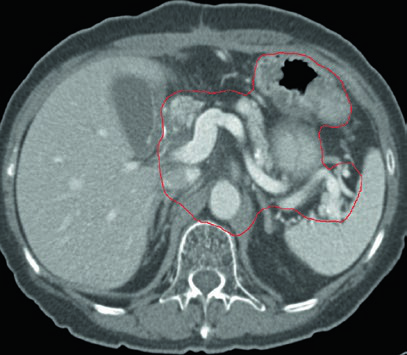

Caso 2: T3N3M0 Adenocarcinoma do Corpo — Gastrectomia Distal

Com doença T3N3, o CTV é extenso: inclui anastomose gastrojejunal, estômago remanescente, artéria celíaca, hilo esplênico e leito tumoral pancreático. Esse cenário exige atenção especial às restrições de dose nos órgãos de risco — particularmente rins e fígado — pois o volume de tratamento é considerável.